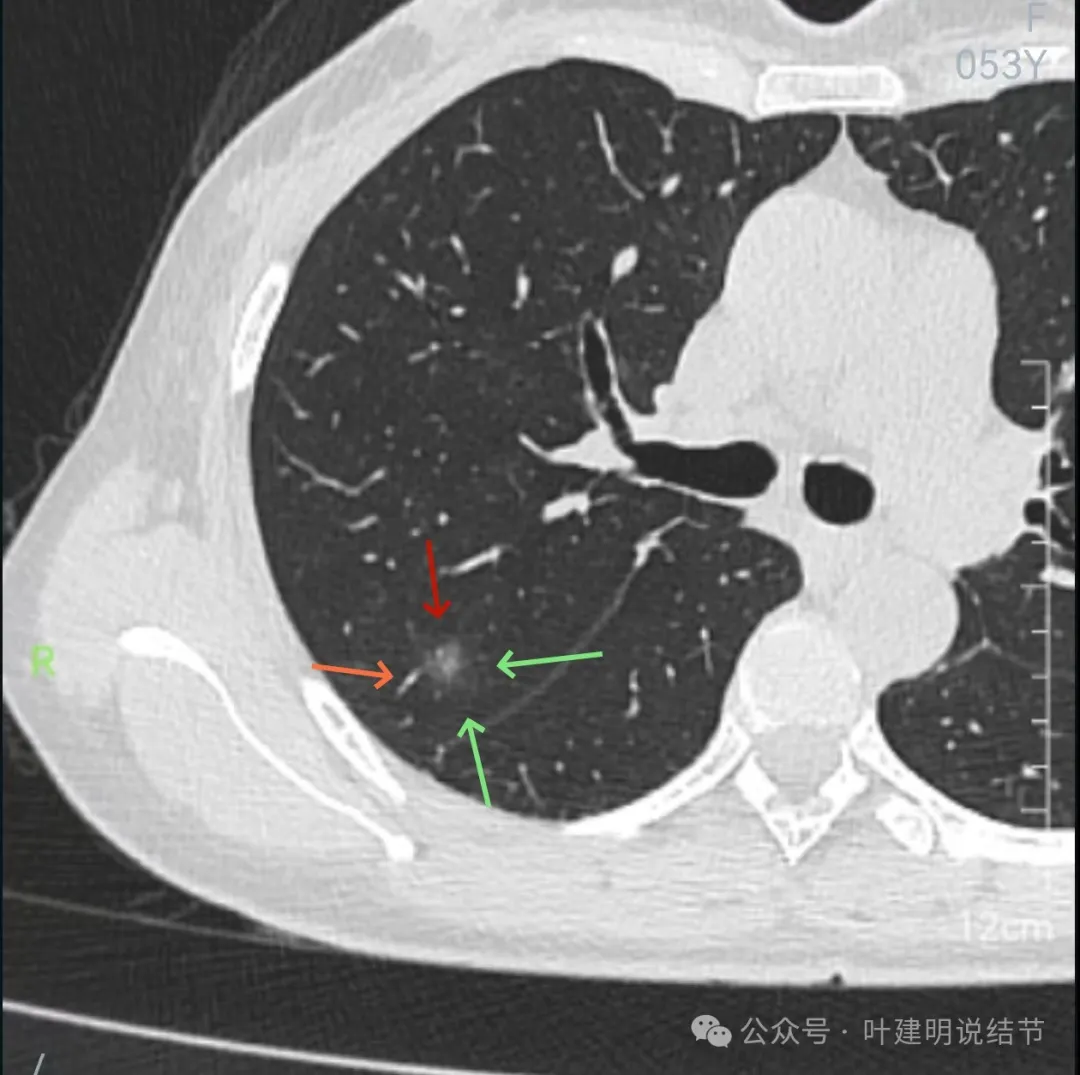

左下叶混合密度结节,边缘有淡的磨玻璃影,瘤肺边界欠清,实性成分明显,略偏散。

右下叶以及左下叶实性结节,缺乏膨胀性,没有收缩力,紧贴胸壁或膈肌无牵拉凹陷。

蓝色的是实性的小结节,缺乏膨胀性,两次检查都有,没有变化,考虑是良性的;红色的这些事10月份检查新增的,这两处比较明显的9月份的时候就是绿色框起来这个区域,当时是没有的。短时间内出现、多发病灶、边缘模糊、轮廓欠清,没有恶性特征,与炎性病变符合。建议查查隐球菌方面的化验,如此结果阳性,请呼吸内科或感染科处理。意见供参考!

实性成分在灶内看,也是界限不清,磨玻璃部分淡而糊。

整体感觉像病灶中间偏实性些的成分伴外周晕征。

边缘区域离叶间裂更近,仍无牵拉。

几乎贴着叶间裂了,仍无任何牵拉影响。

病灶密度边缘部分也不均,离叶间裂近而没有影响。

上图病灶已经贴着叶间裂,但仍显示是平直的,没有任何牵拉影响。